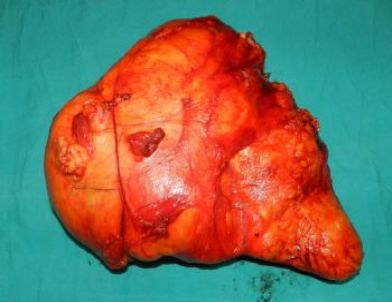

Giresun’un Görele ilçesinde, karın şişliği yüzünden hastaneye başvuran kadının karnından, ameliyatla 15 kilogram ağırlığında ur çıkarıldı.

Genel Cerrahi Uzmanı Opr. Dr. Aziz Ahmet Surel, bu büyüklükte bir kitlenin tıpta nadir görüldüğünü belirterek “Hastamız karın bölgesindeki şişlik şikayetiyle bize başvurdu. Yaptığımız tahliller sonucu karın bölgesinde büyük bir kitle olduğunu belirledik. Daha sonra hasta ameliyata alındı. Ameliyatta hastanın karnından yaklaşık olarak 45 santimetreye 30 santimetre boyutlarında 15 kilogram ağırlığında bir kitle başarılı bir ameliyatla çıkarıldı. Bu kitle karın içersinde o kadar bir yer kaplamış ki normalde olması gereken bağırsaklar üçte bir alana sıkışmış vaziyetteydi. Kitleyi çıkardık hastamızı 3 gün boyunca yoğun bakımda takip ettik. Hastamız 7 gün içinde taburcu oldu. Çıkan kitleyi patolojik incelemeye gönderdik. Patolojiden çıkan sonuca göre kalan tedavi sürecini planlayacağız” dedi.